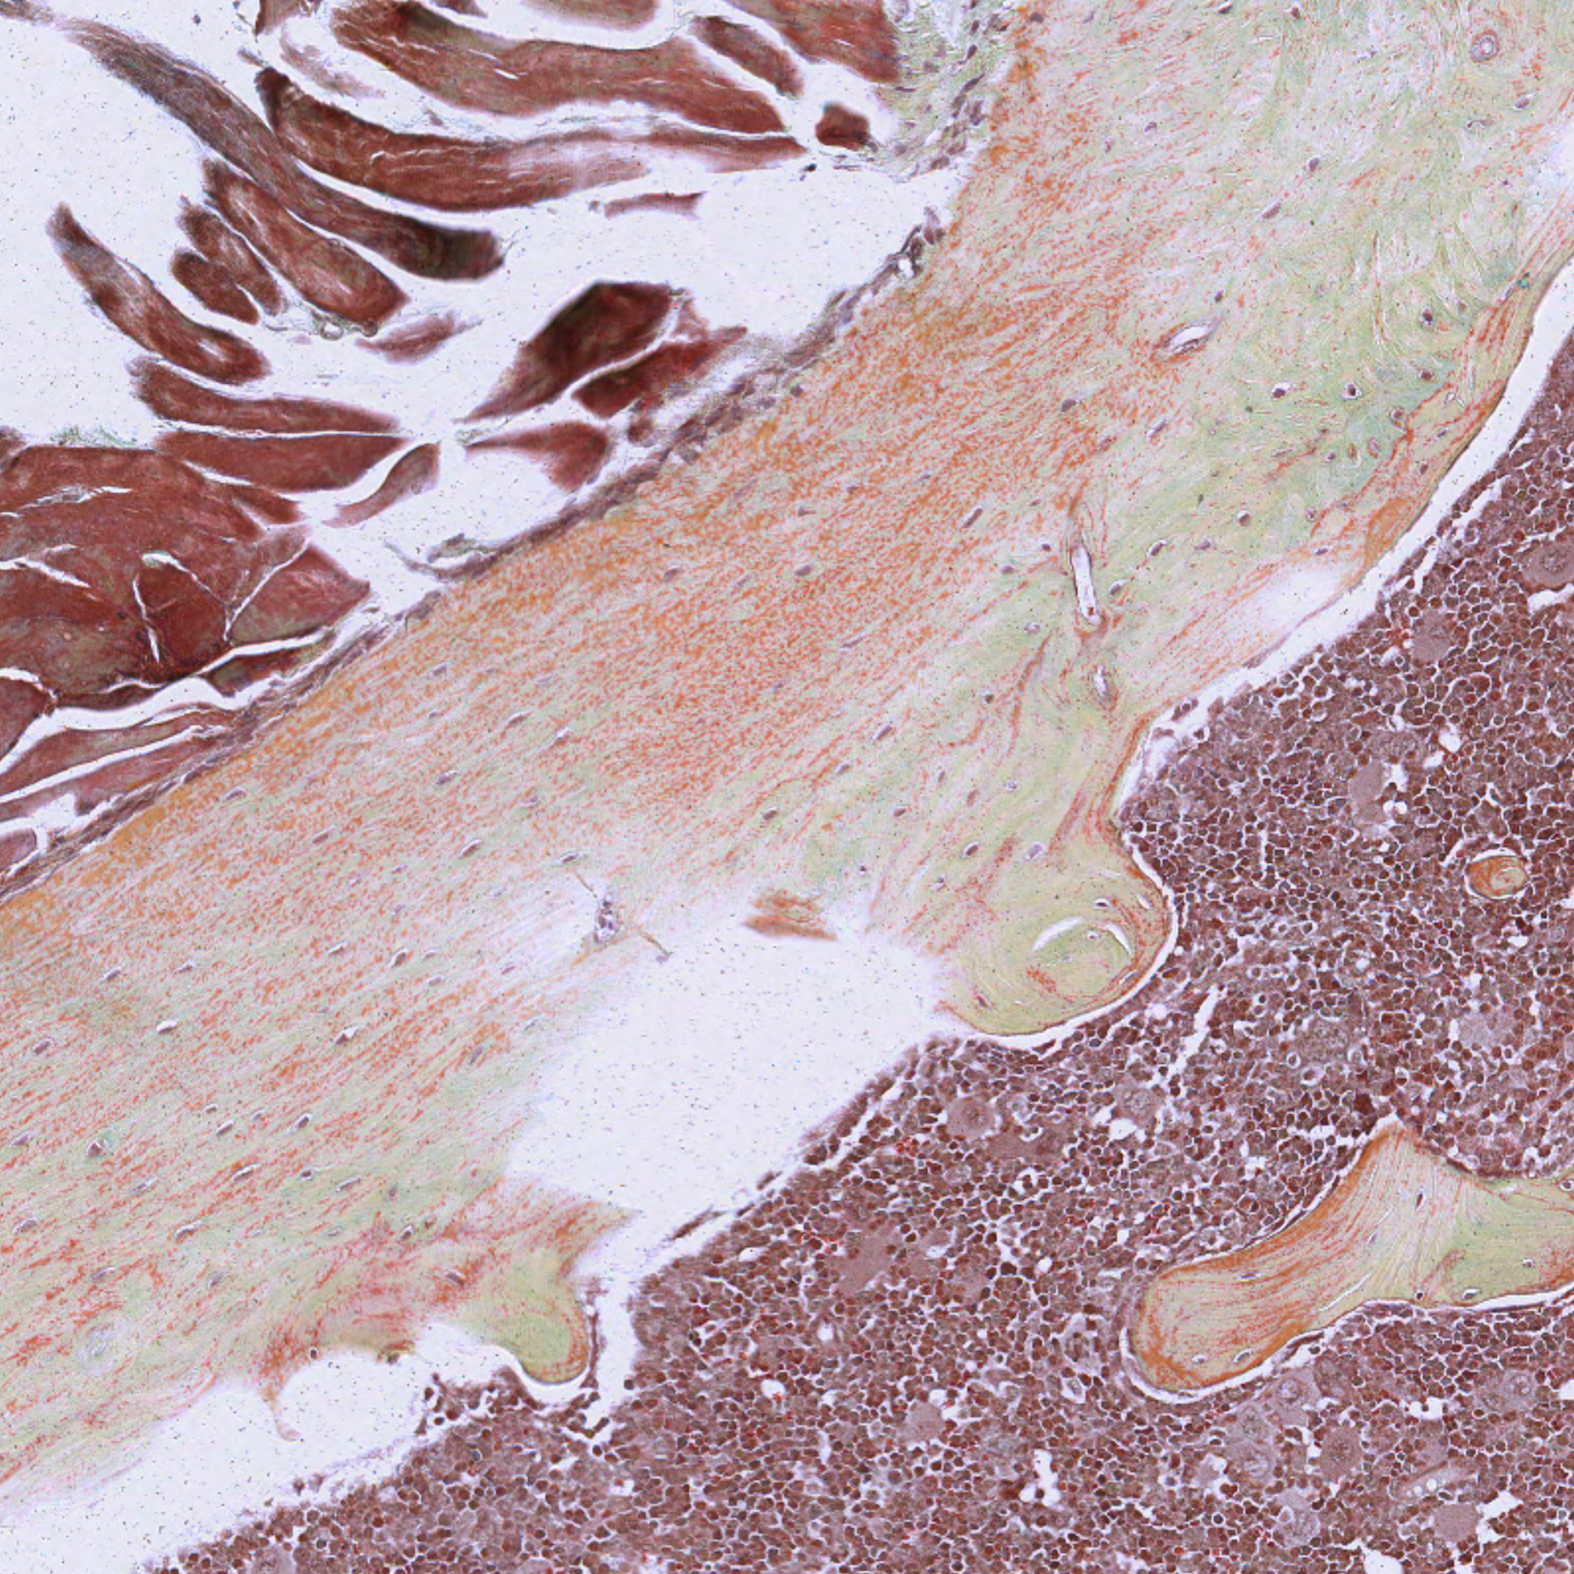

The blue colour in the pentachrome stain kit represents mucin and indicates the progression of bone remodelling. The pentachrome stain kit helps to visualize the bone material before ossification. Chondroids and the matrix are also well differentiated and visualized. Further, striations of the muscles, bone, and cartilage are well visualized with the pentachrome stain kit.